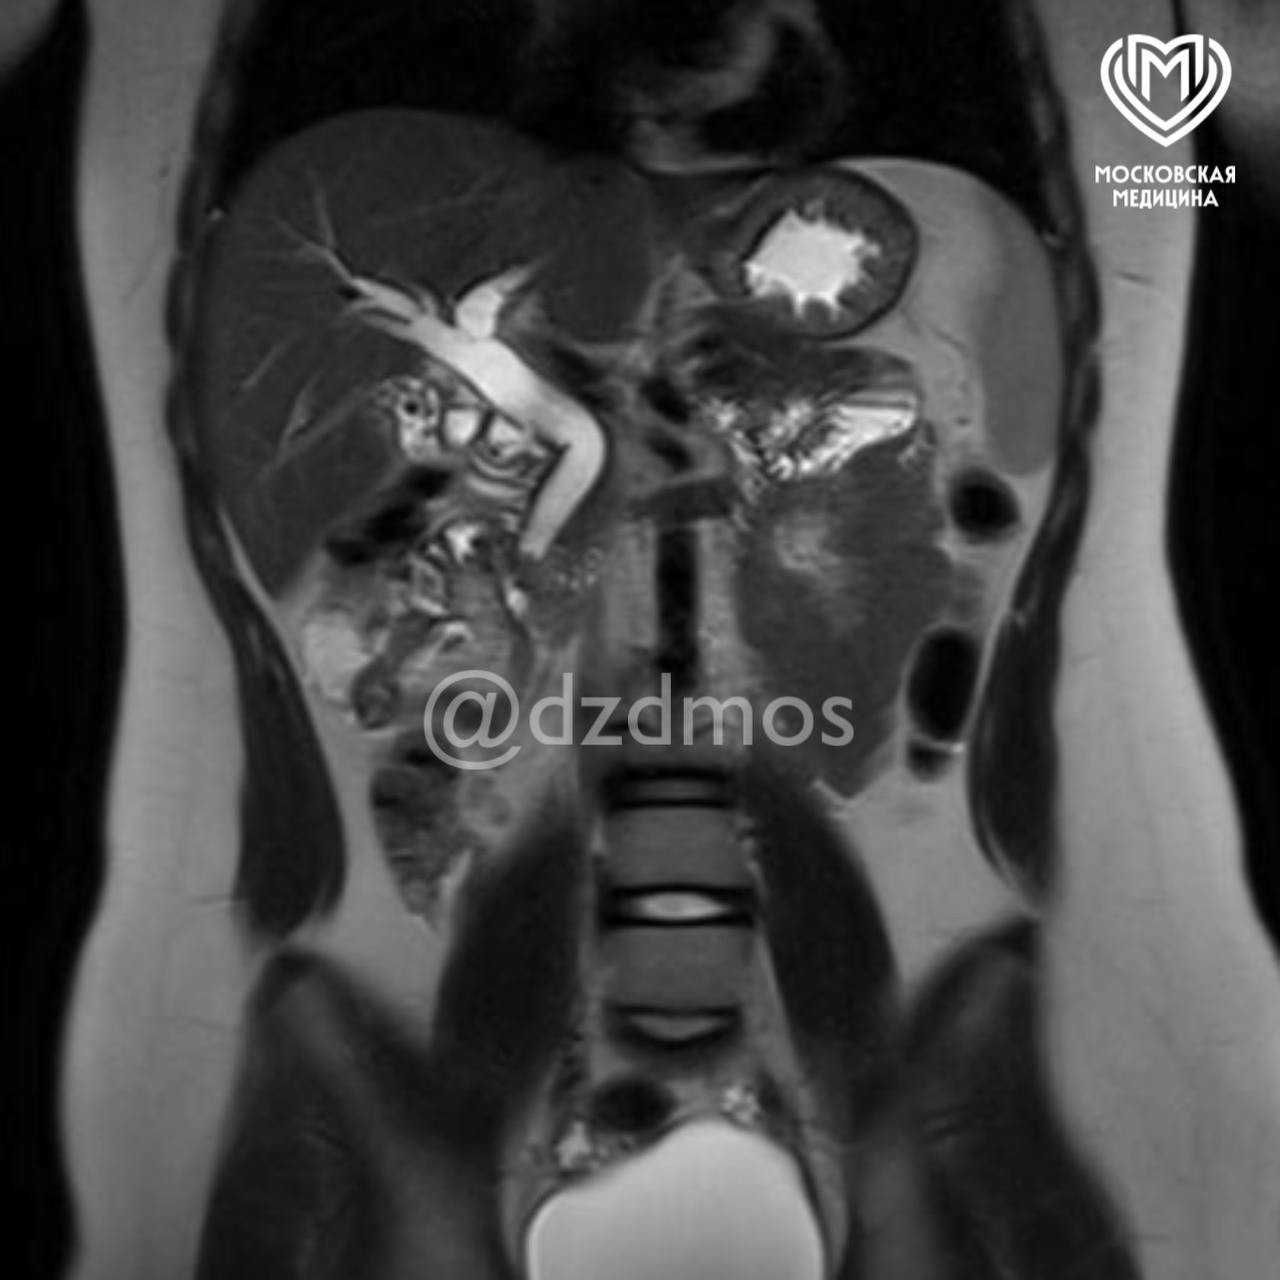

Ребенок поступил в медицинское учреждение с болями в животе, рвотой и общей слабостью. Обследование показало, что в желчном пузыре ребенка скопилось огромное количество камней диаметром до 3 мм. Один из них перекрыл общий желчный проток, что угрожало жизни девочки.

«Ребенку сделали эндоскопическую папиллосфинктеротомию: специальным аппаратом рассекли сосочек, впадающий в желчный проток, расширили его мышечное кольцо и извлекли камень. Вторым этапом удалили желчный пузырь, полностью забитый камнями», — рассказали в пресс-службе депздрава.